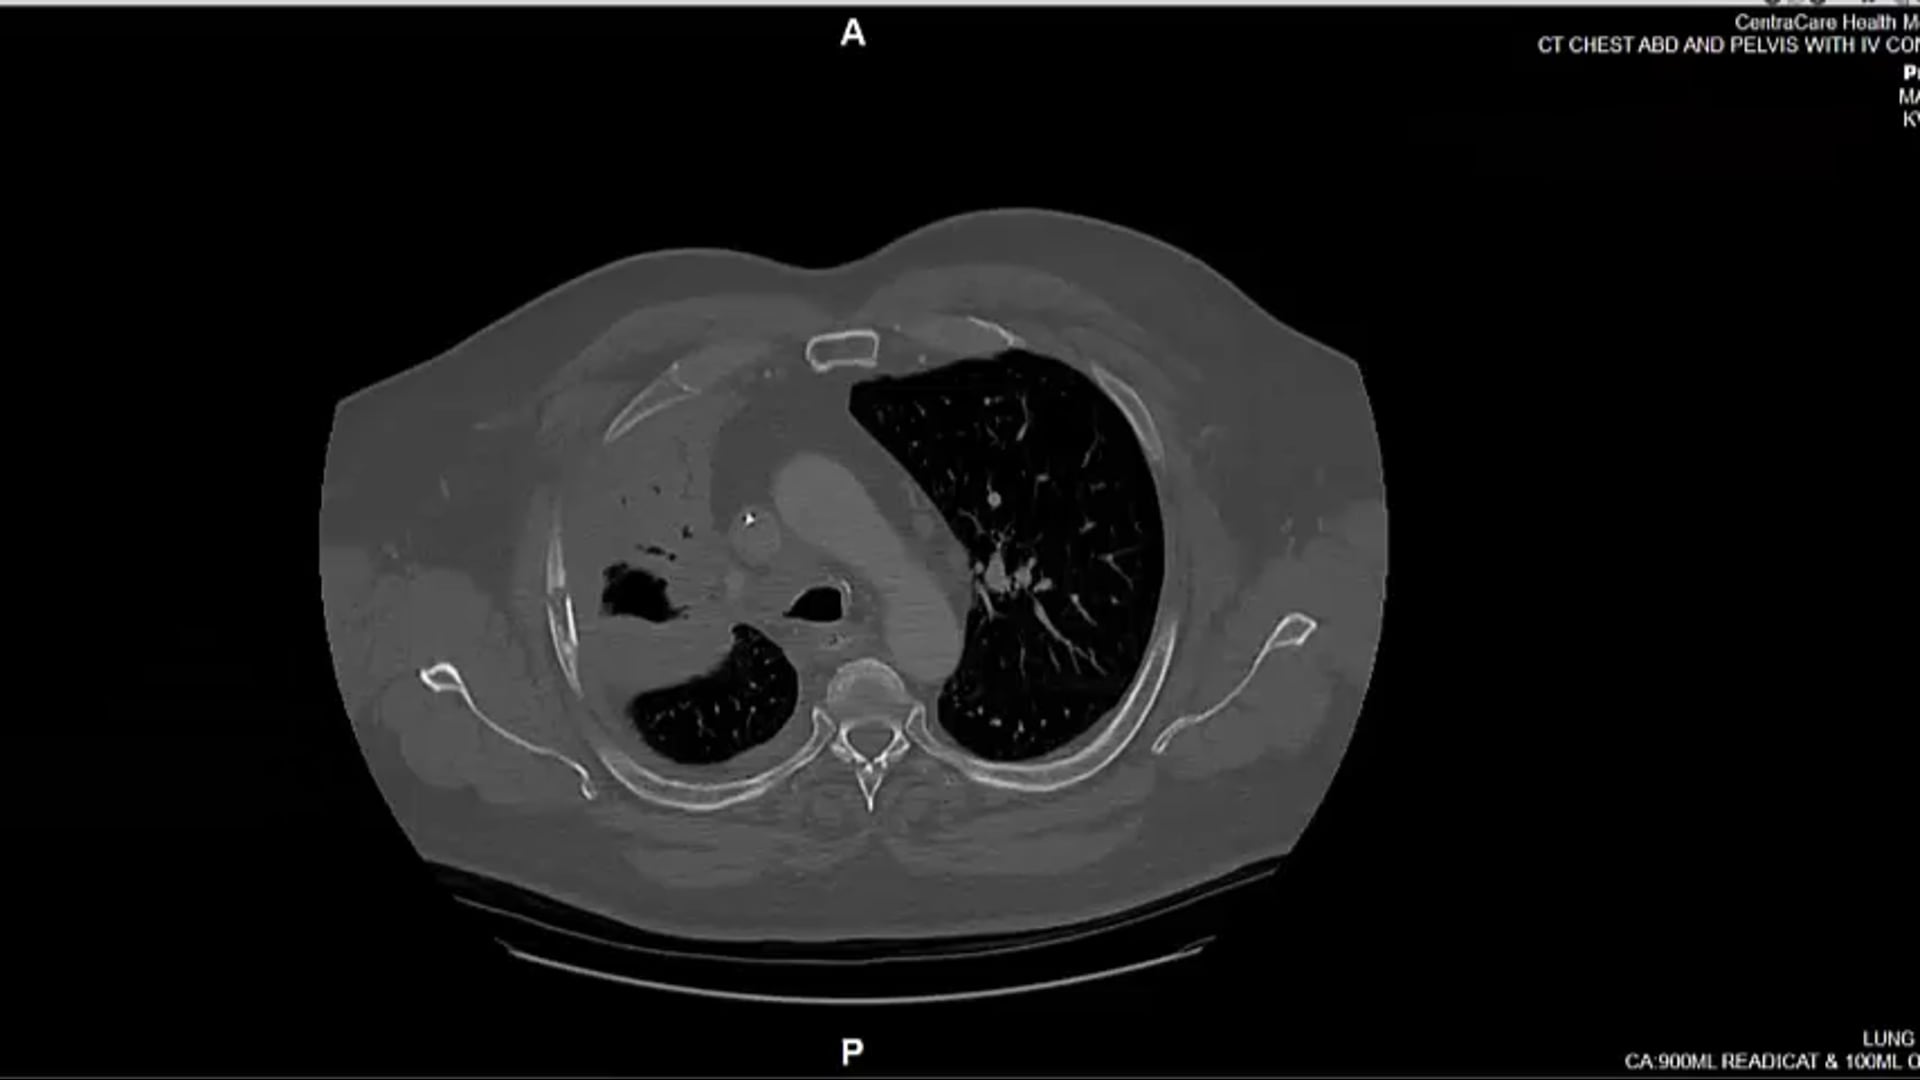

02/10/2022 - Dr Candice Johnstone - Radiation Oncology - Lung and Palliative

10/06/2022 - Dr. Candice Johnstone - Radiation Oncology - Lung/Esophageal

refused chemotherapy, tumor, dose-volume constraints, CORSAIR, 55Gy 20 regimen, SBRT, CTV, clinical target volume, fractionation